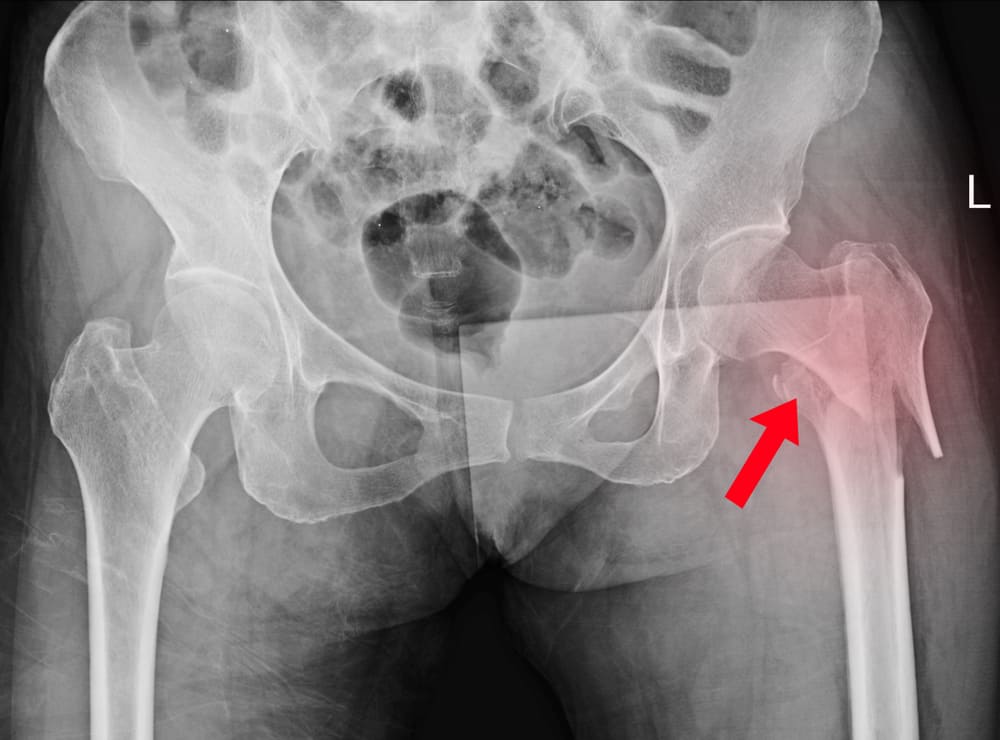

На 3 стадии асептического некроза развиваются характерные анатомические изменения: расширение суставной щели, уплощение костной ткани, укорочение шейки бедра и прочие характерные визуальные признаки. Субъективные ощущения присутствуют. Заболевание сопровождается болью разной степени выраженности. Это разгар патологического процесса.

На 4 стадии АНГБК процесс постепенно стабилизируется. Наблюдается временное затухание клинической картины. Усиления расстройства не происходит.